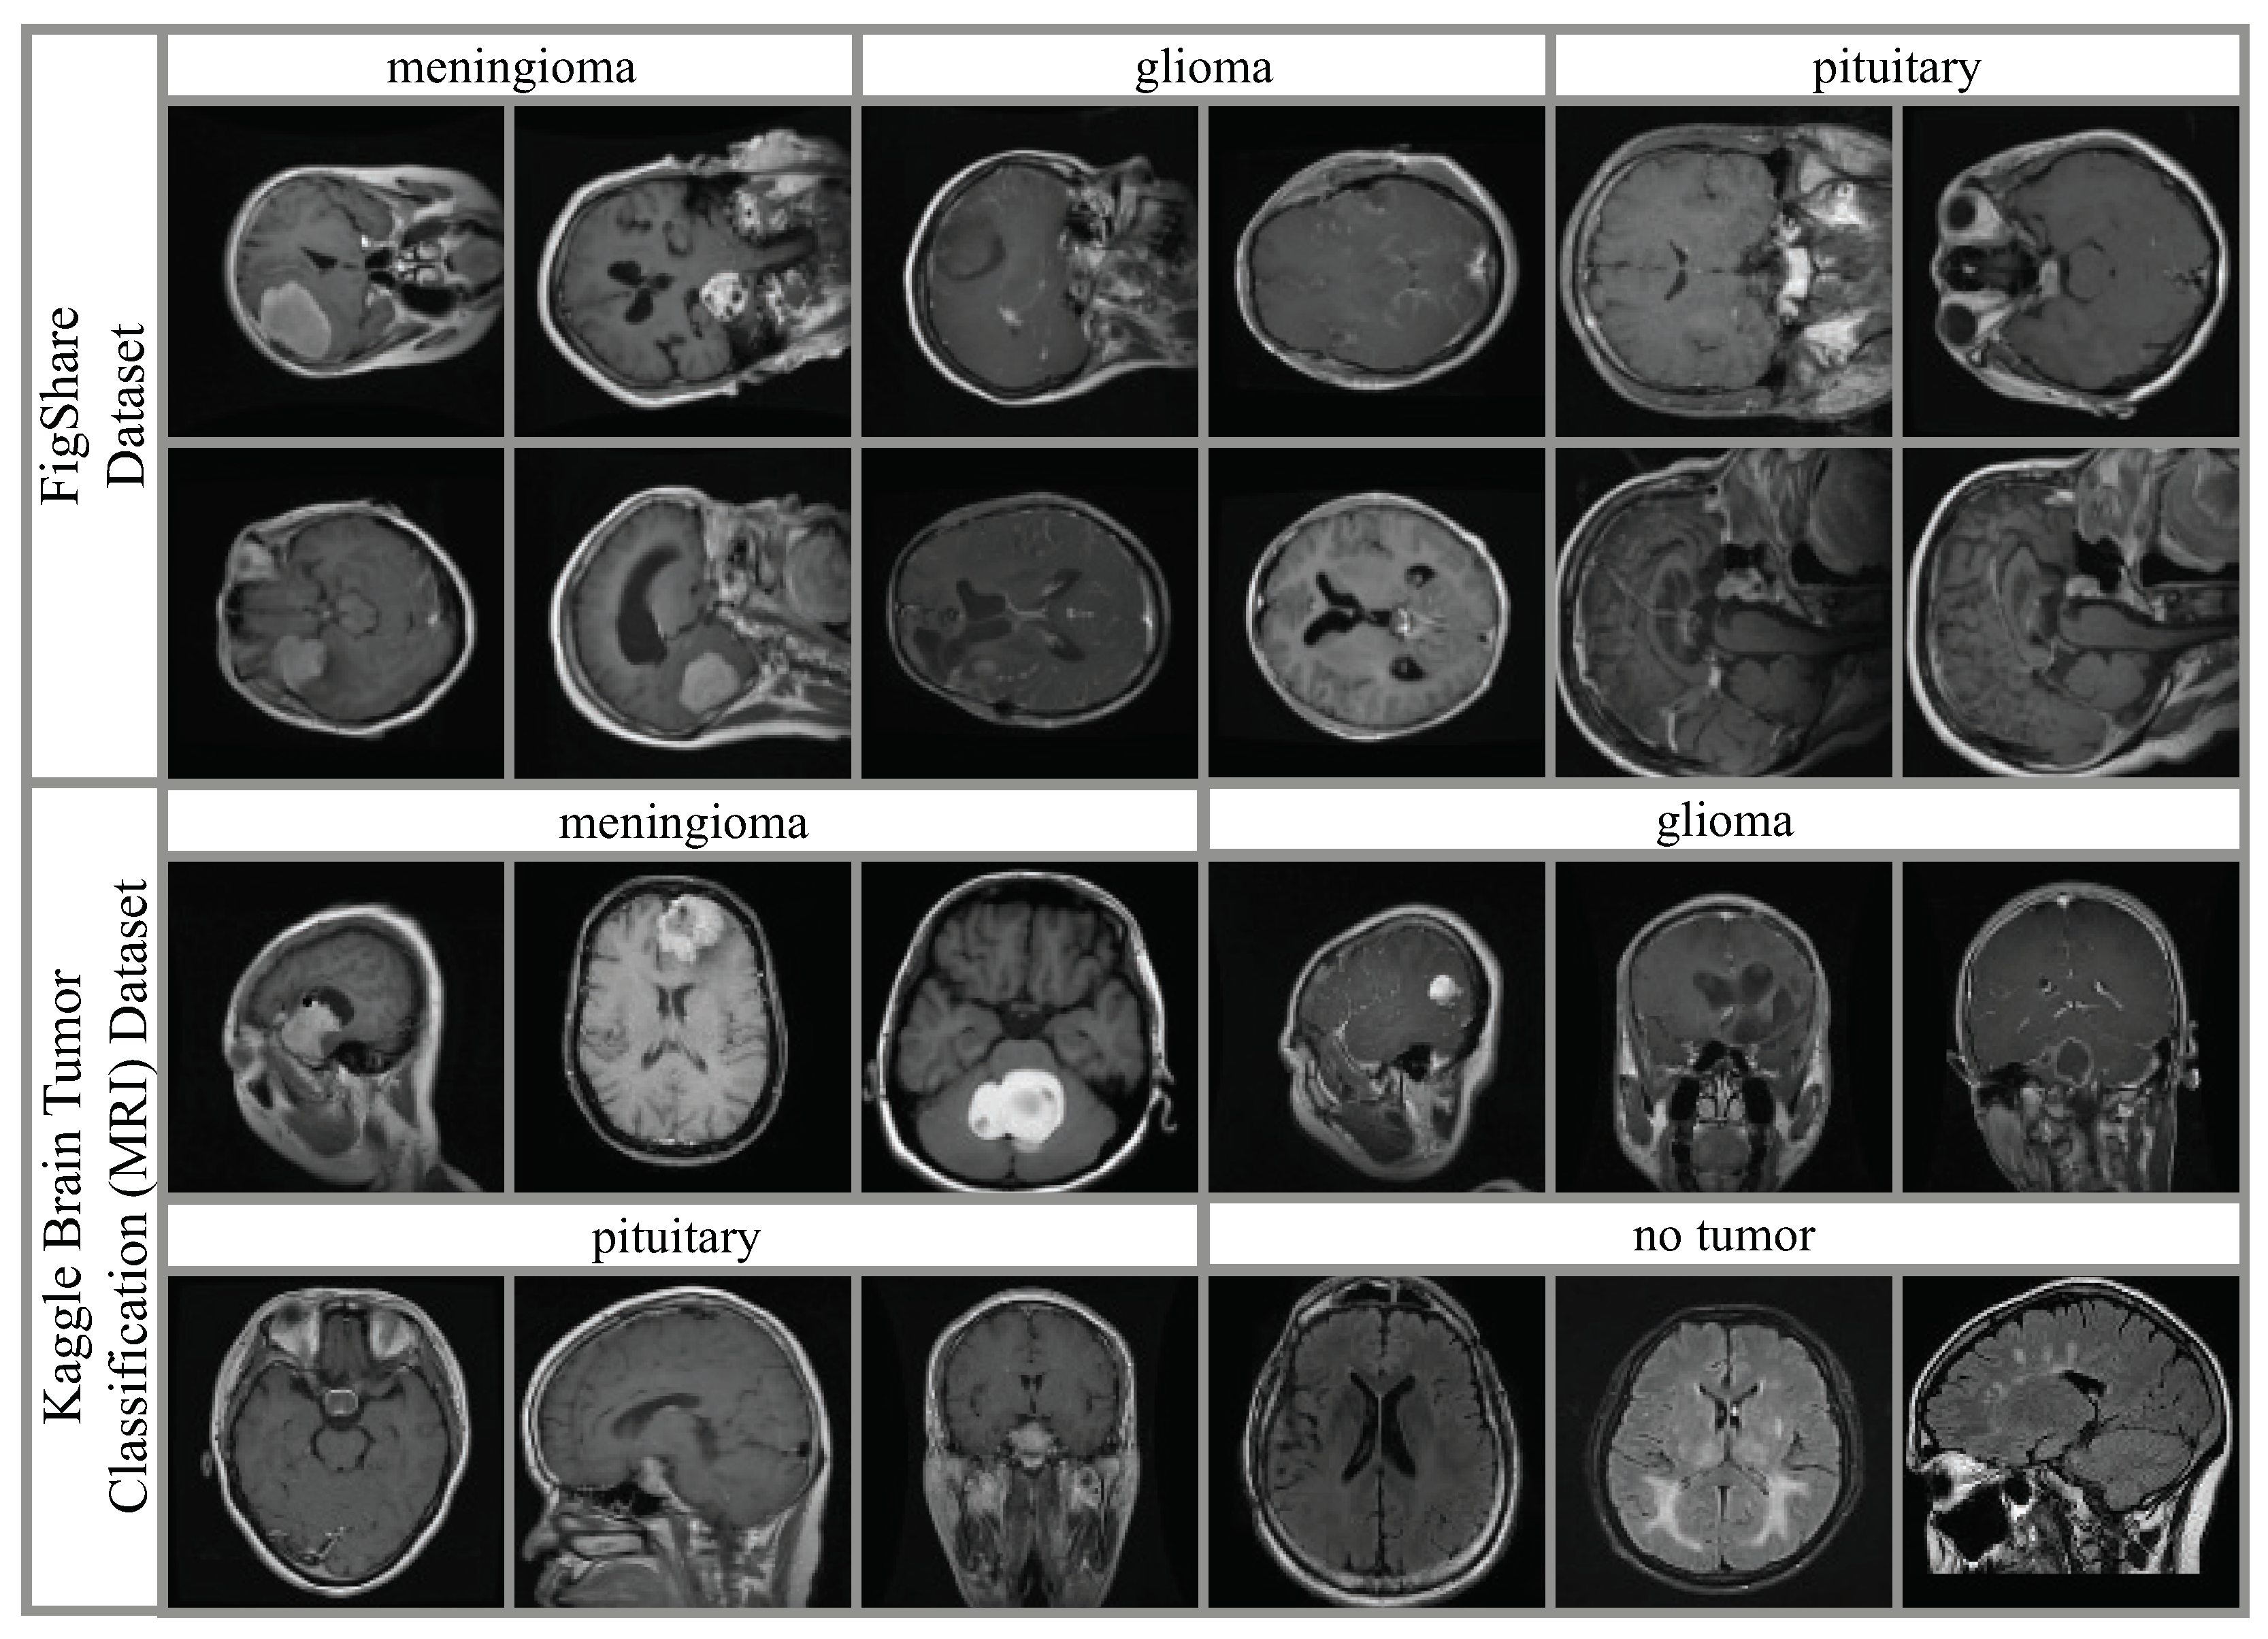

4.1. Datasets and Hyperparameter Settings

- Brain Tumor Classification (MRI). Available online: https://www.kaggle.com/datasets/sartajbhuvaji/brain-tumor-classification-mri (accessed on 1 March 2024).

- Figshare Brain Tumor Dataset. Available online: https://figshare.com/articles/dataset/brain-tumor-dataset/1512427 (accessed on 1 March 2024).